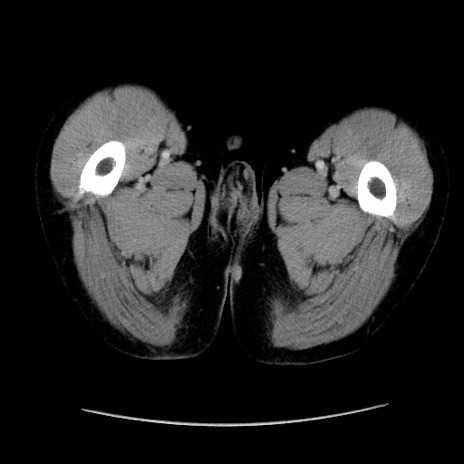

冠状断像